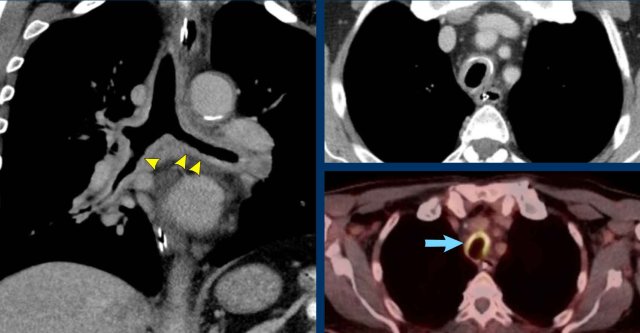

Image

Diffuse

circumferential wall thickening of the trachea and central bronchi with

uptake on FDG-PET scan (blue arrow) in a 72 y.o male after tracheostomy due to

complicated thyroidectomy.

Clinically labelled as low-grade infectious,

despite the fact that no specific pathogen was cultured.